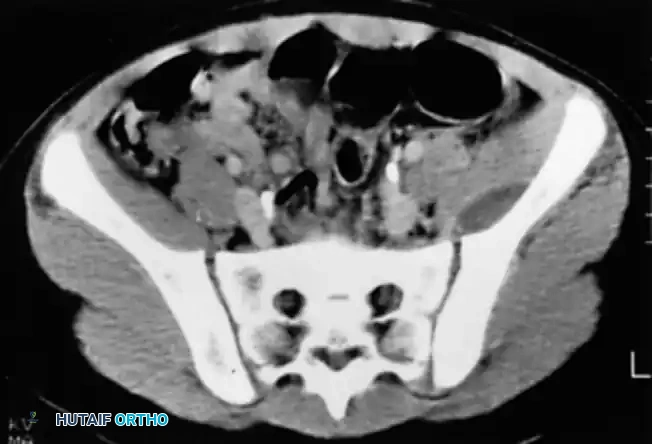

Computed Tomography (CT)

CT scanning is highly effective for determining the extent of cortical destruction and medullary involvement. Pus within the medullary cavity replaces normal marrow fat, resulting in increased radiodensity (higher Hounsfield units) on the CT scan.

Image

Fig. 15-2 Pelvic abscess in a child as seen on CT scan, demonstrating a large, loculated fluid collection adjacent to the ilium.